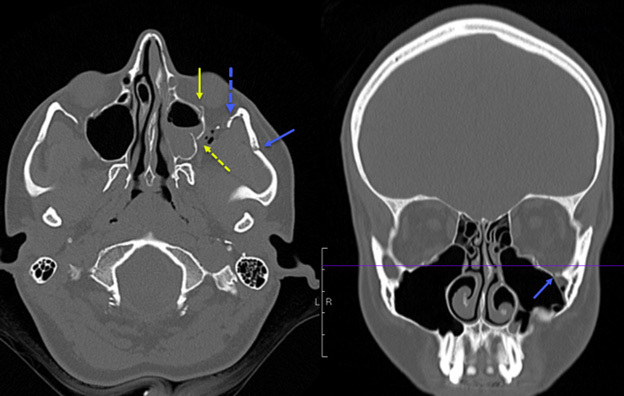

Figure 1 shows a slice of a CT scan in both the axial and coronal planes that provides an example of a ZMC fracture in a pediatric patient. The image demonstrates an anterior and posterior maxillary sinus wall fracture, zygomatic arch fracture, inferior orbital rim fracture, and lateral orbital rim fracture.

Figure 1. Computed Tomography Scan |

The image demonstrates an anterior and posterior maxillary sinus wall fracture, zygomatic arch fracture, inferior orbital rim fracture, and lateral orbital rim fracture. Image courtesy of Mantosh S. Rattan, MD, Radiologist, Orlando Health Arnold Palmer Children’s Hospital, Orlando, FL. |